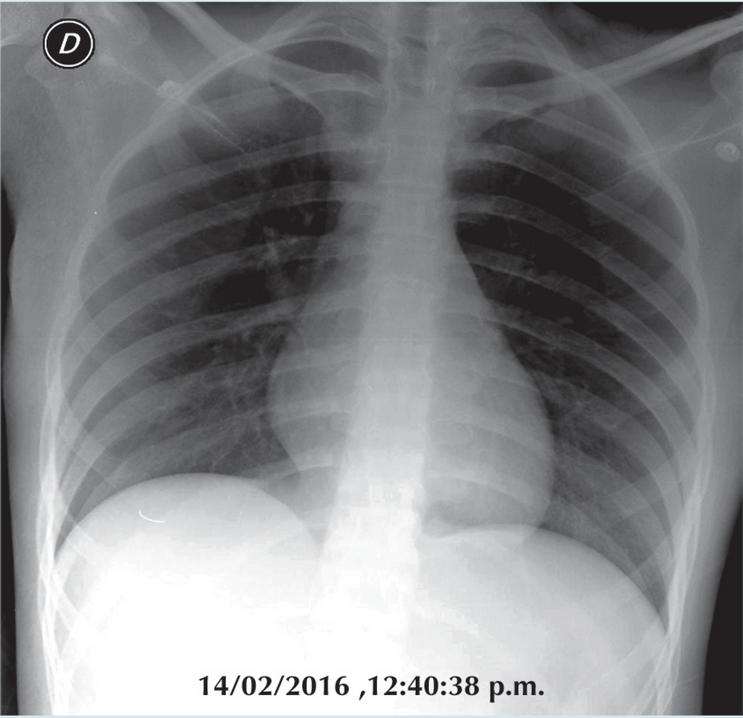

Con el tratamiento instituido, la niña entró en remisión y desparecieron la masa mediastinal y los datos de afección mamaria (Figura 5). La autopsia aclara el cuadro final con una complicación pulmonar por Toxoplasma gondii; es una complicación rara de la inmunosupresión; sin embargo, de los parásitos intracelulares es el más usual. Se describe en el paciente inmuno comprometido con opacidades nodulares gruesas o con un patrón retículo nodular grueso, difuso, como el presentado finalmente por nuestra paciente, con una progresión rápida (Figura 6).

Esto condujo de inmediato a la instalación de un esquema de quimioterapia para linfoma de alto riesgo como corresponde al tipo histológico y a su extensión en sistema nervioso y en mamas. Se logró la remisión; la masa mediastinal desapareció así como las manifestaciones neurológicas y la hipertrofia mamaria. Durante el periodo de consolidación nuestra paciente estuvo siete meses sin evidencia de actividad neoplásica, con LCR y médulas óseas negativas y con complicaciones atribuibles a efectos de la quimioterapia y que fueron resueltos.